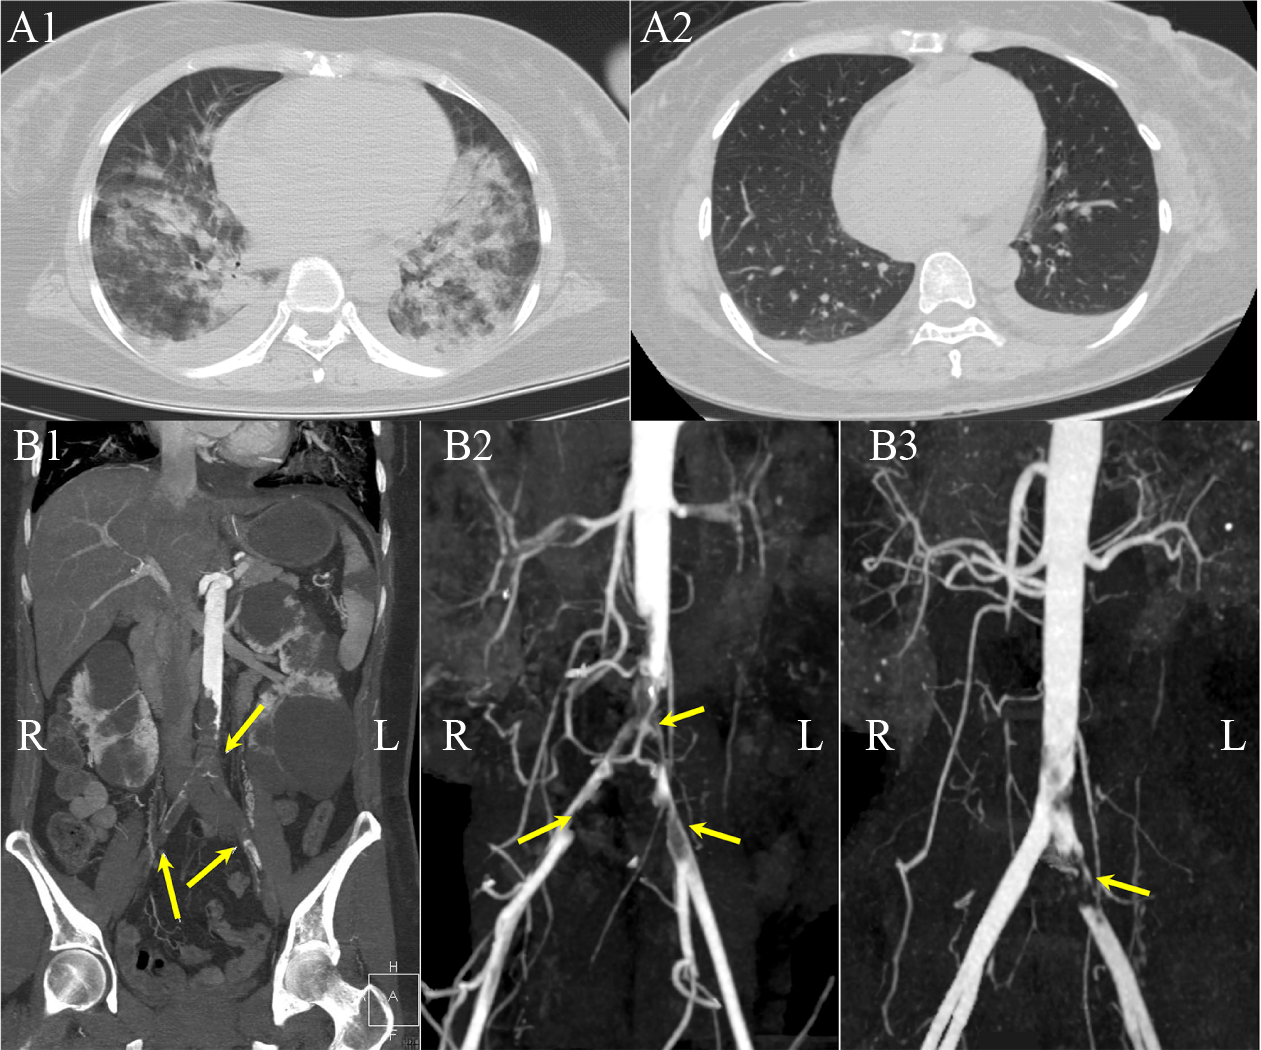

The 12-lead electrocardiogram (ECG) and cardiac monitoring revealed sinus tachycardia accompanied by anterolateral and inferior ST-segment elevation (Fig. S1). Echocardiography indicated left ventricular end-diastolic diameter of 47 mm, left atrial diameter of 35 mm, left ventricular ejection fraction (LVEF) of 26%, significantly reduced regional ventricular wall motion (the inferior, anterior, and lateral walls of the left ventricle extending to the apex), a small amount of pericardial effusion, and left ventricular mural thrombosis. The enhanced computed tomography (CT) and angiography of the head, chest, abdomen, pelvis, and lower limbs yielded several findings. First, acute scattered lacunar cerebral infarctions were identified in the right basal ganglia, left temporal lobe, and bilateral frontoparietal lobes. Second, there was evidence of pulmonary edema with bilateral pleural effusions and superadded chest infection (Fig. 1A1). While no significant stenosis was observed in the coronary arteries, a widespread striated hypodense subendocardial myocardial shadow suggestive of left ventricular mural thrombosis was noted. Notably, complete aortic occlusion was observed, due to aortic thrombosis affecting the infrarenal abdominal aorta and branches of the superior mesenteric artery, bilateral common iliac arteries, and the internal and external iliac arteries (Fig. 1B1, arrow). The patient also exhibited multiple infarctions in the spleen, polycystic kidney, and polycystic liver (Fig. S2). Based on these findings, the preliminary diagnosis for the patient was influenza virus type A-related FM with abdominal aortic occlusion due to in situ acute thrombosis and peripheral nerve damage.

Following two days of treatment, the patient experienced a marked improvement in her condition. She regained complete consciousness, ability to elevate both legs independently, and had no sensations of chest tightness or shortness of breath. However, the patient complained of severe pain in both lower limbs, which was alleviated with fentanyl for analgesia. Her blood pressure also improved, reaching 100/70 mmHg. Moreover, the previously noted lung rales significantly reduced, leading to weaning off of the respirator. After five days, the patient reported significant alleviation of pain and abnormal sensation in both feet. Her vital signs returned to normal. Physical examination revealed the absence of moist rales in both lungs, improved heart sounds, and a heart rate of 80–90 beats per minute. Additionally, her bilateral foot-drop condition was alleviated, the skin temperature in both lower limbs normalized, and bilateral dorsal pedal pulses were palpable. Subsequent CT scans indicated positive developments including a partially patent aorta and restored blood flow in the bilateral iliac and femoral arteries (day 4) (Fig. 1B2, arrows). To further minimize aortic thrombosis, intra-aortic recombinant tissue plasminogen activator (rt-PA) injection, and subsequent thrombus aspiration via the right femoral artery approach were performed (day 6). As a result, the patient’s lower extremity pain was significantly relieved, and her serum CK levels decreased to 12 797 U/L. On day 7, a significant improvement in lung infection and pulmonary edema was observed (Fig. 1A2). A follow-up CT suggested that the patient's aorta and right iliac artery were essentially well-filled, while the left iliac artery still exhibited a filling defect due to residual thrombus (day 11) (Fig. 1B3, arrow). Concurrently, biomarkers such as CK, hs-cTnI, NT-proBNP, and plasma cytokines all showed significant decrease (Fig. 3). Repeat abdominal CT (day 14) suggested a right rectus abdominis hematoma (58 mm× 31 mm × 128 mm) (Fig. S3). Consequently, anticoagulation therapy was shifted to rivaroxaban at a dose of 15 mg twice per day (Fig. 2). After 19 d of comprehensive treatment, the patient’s FM and cardiac function improved significantly, with LVEF reaching 50%, leading to her discharge from the hospital (Fig. 3).